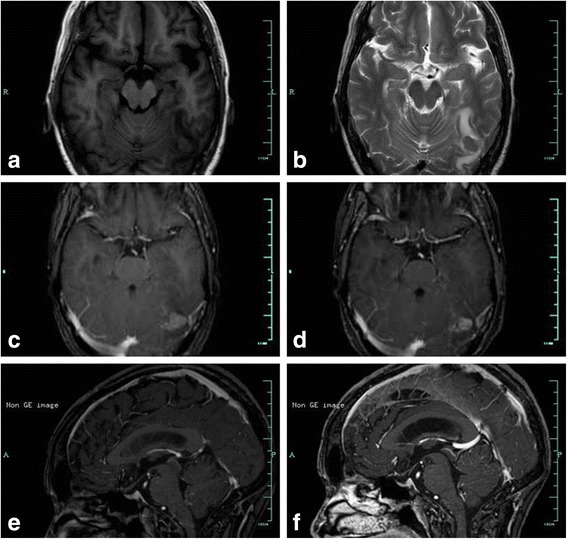

A 53-year-old female was referred to our department from a local hospital for further diagnosis and treatment after being diagnosed with a space-occupying lesion in the left occipital lobe. The patient presented with headache accompanied by nausea and vomiting for 10 days. In 2010, she had been diagnosed with and resected for gastric adenocarcinoma. Gadopentetate dimeglumine-enhanced MRI scan (Philips Achieva 3.0 T Dual MRI, 0.1 mmol/kg, immediately after injection) was performed to identify the occipital lesion. On the MRI scan, an ovoid mass with the diameter of 1.6 centimeter can be seen in the left occipital lobe. The mass was hyperintense on T1-weighted images, and iso- to hypointense on T2-weighted images (Fig 2a, b). After administration of meglumine gadopentetate, evident homogeneous enhancement was seen (Fig. 2c). The patient was diagnosed metastatic left occipital tumor from gastric adenocarcinoma, and Gamma knife surgery (GKS) with the marginal dose of 22 Gy was given. Three days after GKS, the patient had one time seizure of absences, and complained of aggravation of the headache. A brain CT scan showed no evidence of the tumor stroke. Considering the possibility of meningeal carcinomatosis, lumbar puncture was performed, but CSF cytology showed no evidence of malignant cells. Gadobutrol-enhanced MRI (Philips Achieva 3.0 T Dual MRI, 0.1 mmol/kg, immediately after injection) was performed, and meningeal disseminations around the cerebellum were detected (Fig 2f) except for the evident homogeneous enhancement mass in the left occipital lobe (Fig 2d). Therefore, a diagnosis of meningeal carcinomatosis was made. Radiotherapy and chemotherapy were recommended, while the patient chose medical treatment and died 2 months later.

Fig. 2.

Gadopentetate dimeglumine-enhanced MRI scan shows an ovoid mass with the diameter of 1.6 centimeter in the left occipital lobe. The mass is hyperintense on T1-weighted image (a), iso- to hypointense on T2-weighted image (b), evident homogeneous enhancement on Gadopentetate dimeglumine-enhanced (c) and gadobutrol-enhanced (d) T1-weighted image. Gadobutrol-enhanced T1-weighted image detects nodular enhancement around the cerebellum (f) while gadopentetate dimeglumine-enhanced T1-weighted image shows no abnormality (e)